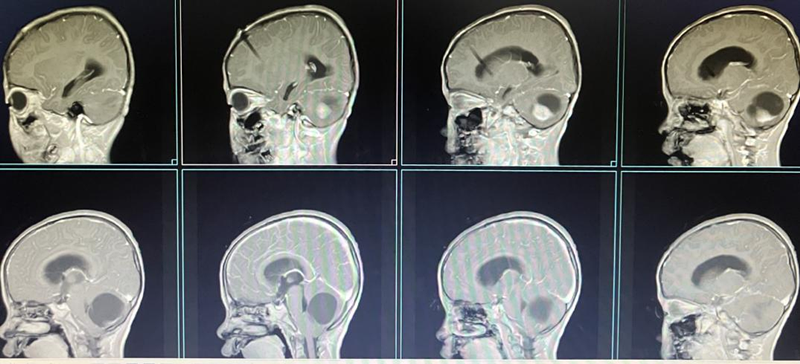

(术后MRI)

(术后10个月复诊)

然而,就在小静入院治疗的第四天,她的病情突然急转直下。当日下午15:52,小静突然呼吸停止,陷入深度昏迷状态。神经外科副主任医师谢正德、蔡艳萍护士等医护人员立刻进行了抢救,抢救成功后,在科主任李松年的指导下,由池超超副主任医师主刀,为女孩进行了急诊开颅手术,将右侧小脑半球肿瘤切除。手术进程顺利,术后48小时复查核磁共振肿瘤全切,无脑积水。